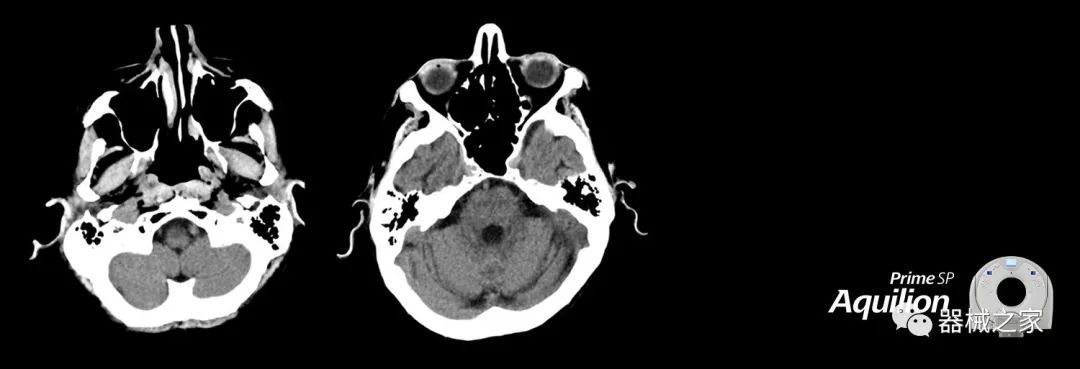

在以患者為中心的放射腫瘤學(xué)領(lǐng)域,計算機(jī)斷層掃描(CT)的可訪問性,可重復(fù)性和靈活性至關(guān)重要。為了建立這些價值,佳能醫(yī)療系統(tǒng)美國公司現(xiàn)在正在擴(kuò)大其放射腫瘤學(xué)CT模擬產(chǎn)品,包括Aquilion Prime SP和Aquilion Lightning 80高級CT系統(tǒng)。除了Aquilion LB之外,Aquilion Prime SP和Aquilion Lightning 80現(xiàn)在還包括放射治療(RT)選項,可為腫瘤學(xué)規(guī)劃提供高質(zhì)量的CT成像和精密工具。

Aquilion Prime SP使設(shè)施能夠處理具有挑戰(zhàn)性的案例,同時為員工提供快速,靈活和高效的解決方案。

兩個CT系統(tǒng)均采用0.5 mm x 80排PUREViSION探測器技術(shù)(可配置并從80-160現(xiàn)場升級),78 cm孔徑,50 cm視野,AIDR(自適應(yīng)迭代劑量減少)3-D和SEMAR(單個)能量金屬神器減少)技術(shù)。